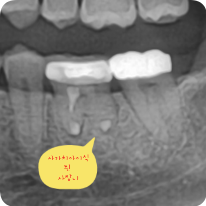

치아에서 피고름이 흘러넘친다면 신경치료로 자연치아 살릴 수 있다는 좋은 싸인

신경치료 첫날 치아에서 피고름이 흘러넘친다면 신경치료로 자연치아 살릴 수 있다는 좋은 싸인입니다.